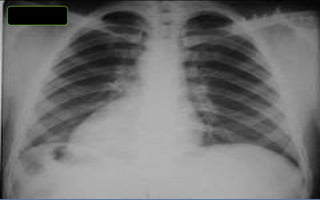

TÓRAX

1. PAR RADIOLOGICO

2. CENTRADO

3. PENETRADO

4. INSPIRADO

Rx de tórax simple o convencional

¿Qué tener en cuenta cuando miramos una Rx tórax frente?

¿Qué buscar en una Rx tórax frente?

¿Qué buscar en una Rx tórax perfil?

INDICE CARDIOTORACICO NORMAL

valor normal es igual o inferior a 0.5 varia según el biotipo y edad del

paciente. (línea roja / suma de líneas azules )